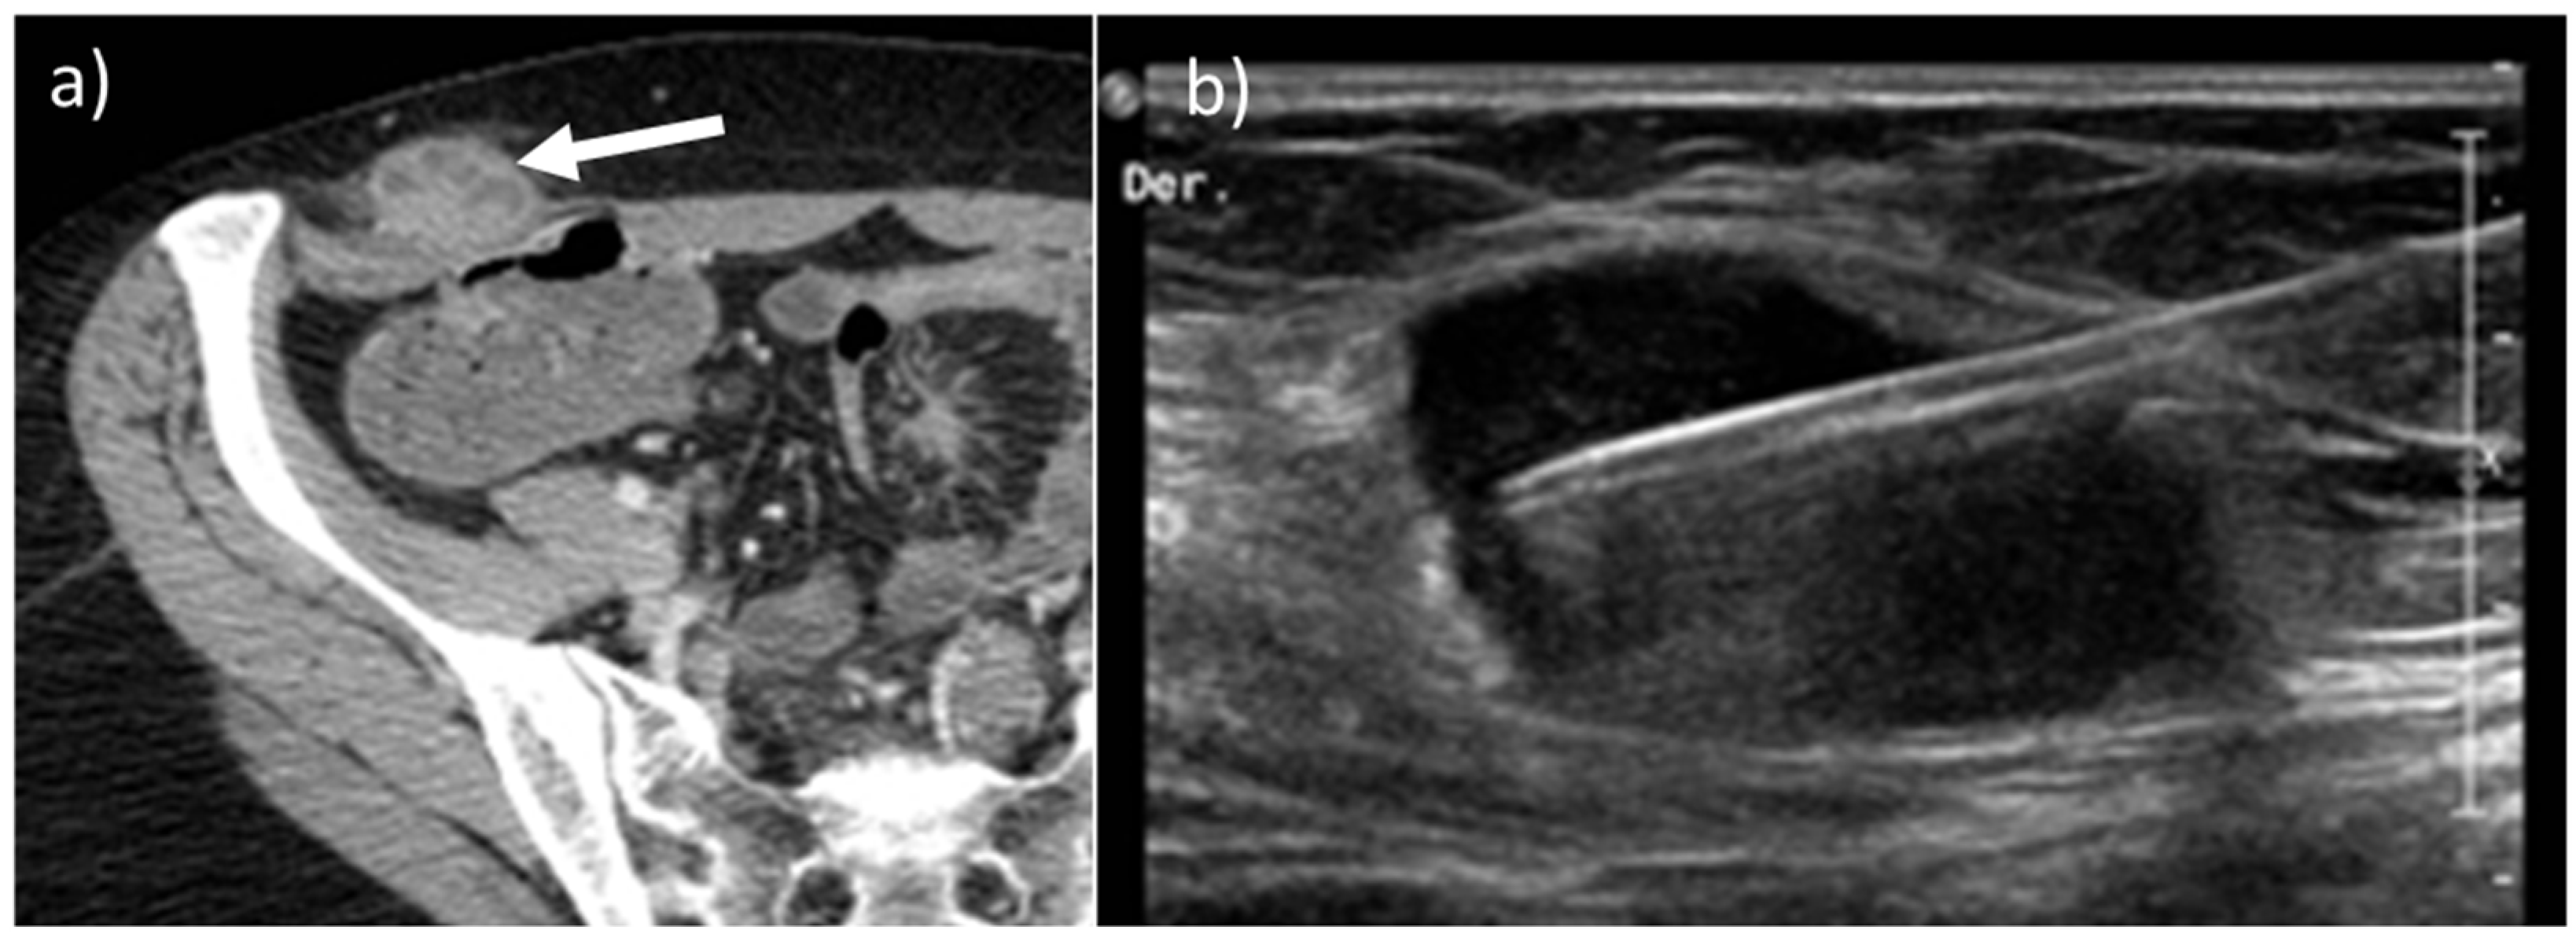

- Desmoplastic Small Round Cell Tumor (DSRCT): rare, highly aggressive sarcoma of adolescents, which primarily involves the serosal surfaces of the abdominal cavity infiltrating the abdominal wall [30,31,32]. Classic findings include bulky multiple, hypoattenuating, soft-tissue masses, with omental, serosal, and rectovesical involvement [31,32] and typical punctate or amorphous calcifications [32]. Modest heterogeneous enhancement is seen on arterial phase, without prolonged enhancement or portal washout [31,32] (Figure 10). On MR, DSRCTs are heterogeneously iso- to-hypointense on T1-w images, with hyperintense foci due to intratumoral hemorrhage [32].